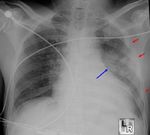

Traumatic Pulmonary Injury

 May occur as injury from direct

force, barotrauma, or rapid

deceleration of organs against

chest wall.

 Injuries may include:

   Pneumothorax

   Hemothorax

   Pulmonary contusion

   Pulmonary injury from blunt thoracic trauma is relatively uncommon in athletics

   Most common injury:

   Symptoms:

   Dyspnea, Chest pain, Dysphonia, Dysphagia, Cough, Hemoptysis

   Management:

   Stabilize ABCs, decision to transport based on severity and mechanism of injury

©Allinahealthsystems                                                                                             13

Lecture 12                                                          June 15, 2018

Return to Play After Pneumothorax

   No specific guidelines

   Gradual goal oriented progression

after radiographic resolution ~3-4

weeks.

   No air travel until 2 weeks after

radiographic resolution. (risk of

tension pneumothorax)